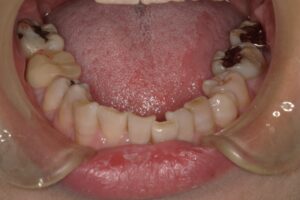

不正咬合

出っ歯(上顎前突)や開咬などの不正咬合も②と同じ理由で起こり、結果としてガミースマイルを引き起こす原因になります。噛み合わせによって唇が閉じにくくなり、笑うと歯ぐきが目立ちやすくなったりします。

小児矯正

上顎が劣成長で出っ歯、開咬、などの不正咬合になっていることが多く、早い時期に上顎の成長方向を正しくコントロールしていくことが望まれます。マウスピース型矯正は素材のしなやかさを使って痛みなく顎を拡げていくことが出来ます。また最近では色々なソリューションをマウスピースでも併用できるようになりました。(前方牽引装置など)女の子は15歳、男の子は18歳でほぼ成長が終わります。時間はあれよあれよという間に過ぎていきます。時期を逃さず取り組み、骨格的ガミースマイルの進行を未然に抑えるとよいでしょう。